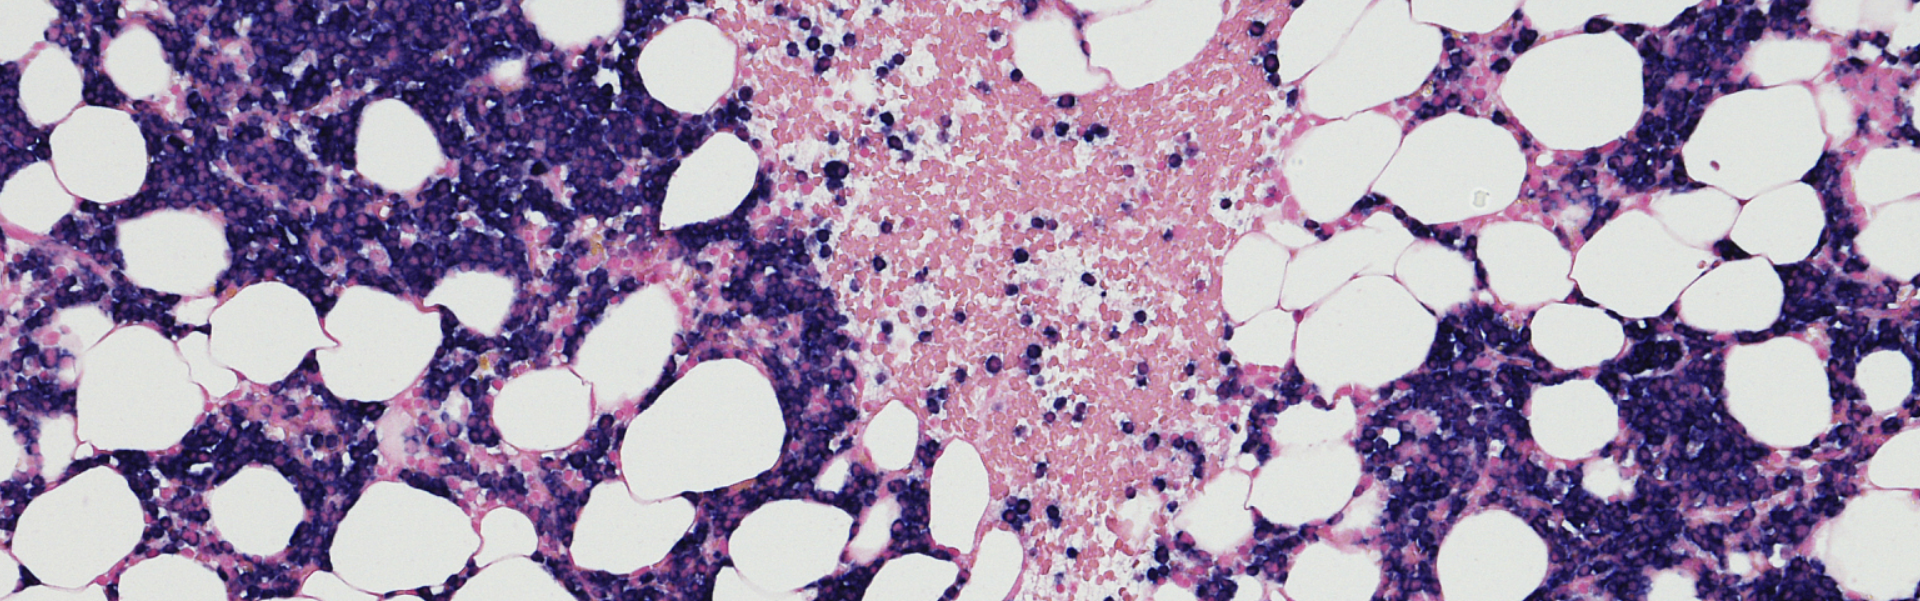

TROP2(滋养层细胞表面抗原2):是一种跨膜糖蛋白,属于细胞表面抗原,在正常组织中低水平表达,而在三阴性乳腺癌、非小细胞肺癌、胃癌、结直肠癌等多种恶性肿瘤中呈现高表达状态,且其表达水平与肿瘤分期、侵袭性及患者生存率密切相关。TROP2可通过激活PI3K/Akt、MAPK等信号通路,调控肿瘤细胞的增殖、凋亡、侵袭和转移,同时其可介导药物内吞,是ADC药物的理想靶点。传统抗体靶向TROP2时易出现脱靶毒性,而纳米抗体可精准识别TROP2特异性表位,结合后高效介导ADC药物内吞,在提升肿瘤杀伤效率的同时,降低对正常组织的损伤,成为TROP2靶向药物优化的核心方向[1]

图1 TROP2 在肿瘤发生信号通路中的核心作用[2]